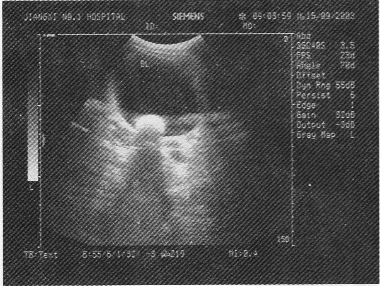

成年男性,血尿伴排尿时尿流中断,超声检查如图,最可能的诊断为

• A.膀胱内凝血块

• B.膀胱结石

• C.膀胱肿瘤

• D.膀胱憩室

• E.腺性膀胱炎